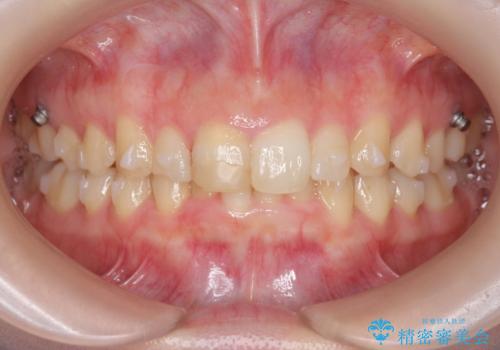

前歯のがたつき 深い噛み合わせを改善したい

- 「前歯のガタつきをきれいにしたい、噛んだ時に下の前歯が見えないことを改善したい」とマウスピース矯正を希望され来院されました。

マウスピースに加え、矯正用マイクロインプラントやゴムを併用し、がたつきや噛み合わせの深さを改善していきます。

ゴムかけやマウスピースの装用時間、しっかりとマウスピースをはめ込むチューウィーをしっかりと使用したことで良好な治療結果を得ることができました。